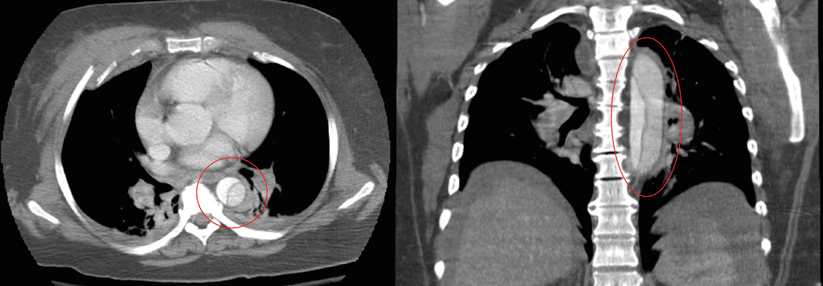

Nicht immer treten die für eine Aortendissektion typischen Zeichen auf. 1: Aorta descendens mit Dissektion. 2: Aortenisthmus. Nicht immer treten die für eine Aortendissektion typischen Zeichen auf. 1: Aorta descendens mit Dissektion. 2: Aortenisthmus. © wikimedia/Dr. Lars Grenacher (CC BY-SA 3.0)

Bei der 57-jährigen Patientin sprach eigentlich alles für ein neurologisches Problem. Während der Physiotherapie war sie mit tonisch-klonischen Krämpfen zusammengeklappt. Der Anfall hatte sich auch im Krankenwagen fortgesetzt. Im Krankenhaus angekommen fiel neben einer rigiden Hyperflexion im Ellbogengelenk und der Hyperextension der linken Hüfte vor allem der niedrige Blutdruck ins Auge, berichten die Herzchirurgin Dr. Rachel Eikelboom und ihr Kollege von der…